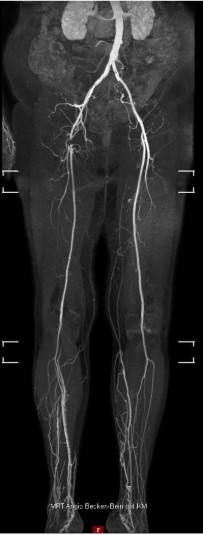

MR-Angiografiya (Şəkil 1):

- Sağ A. femoralis communis-in tam tutulmas

- AFS və APF kollaterallar vasitəsilə yenidən qanla dolu

- Aşağı hissədə yüksək dərəcəli daralmalar yoxdur, yaxşı üçdamarlı qan axını mövcuddu

- Sol tərəf: patologiya aşkar edilməyib

Şəkil 1.Çanaq və ayaq arteriyalarının MR-angiografiyası sağ A. femoralis communis-in tıxanmasını göstərir. A. femoralis superficialis və A. profunda femoris açıqdır.Sağ tərəfdə baldırın yuxarı hissəsində (proksimal hissəsində) üç damarla təchizat mövcuddur.Baldırın aşağı hissəsində (distal hissəsində) venoz strukturların üst-üstə düşməsi bu sahənin qiymətləndirilməsini məhdudlaşdırır.